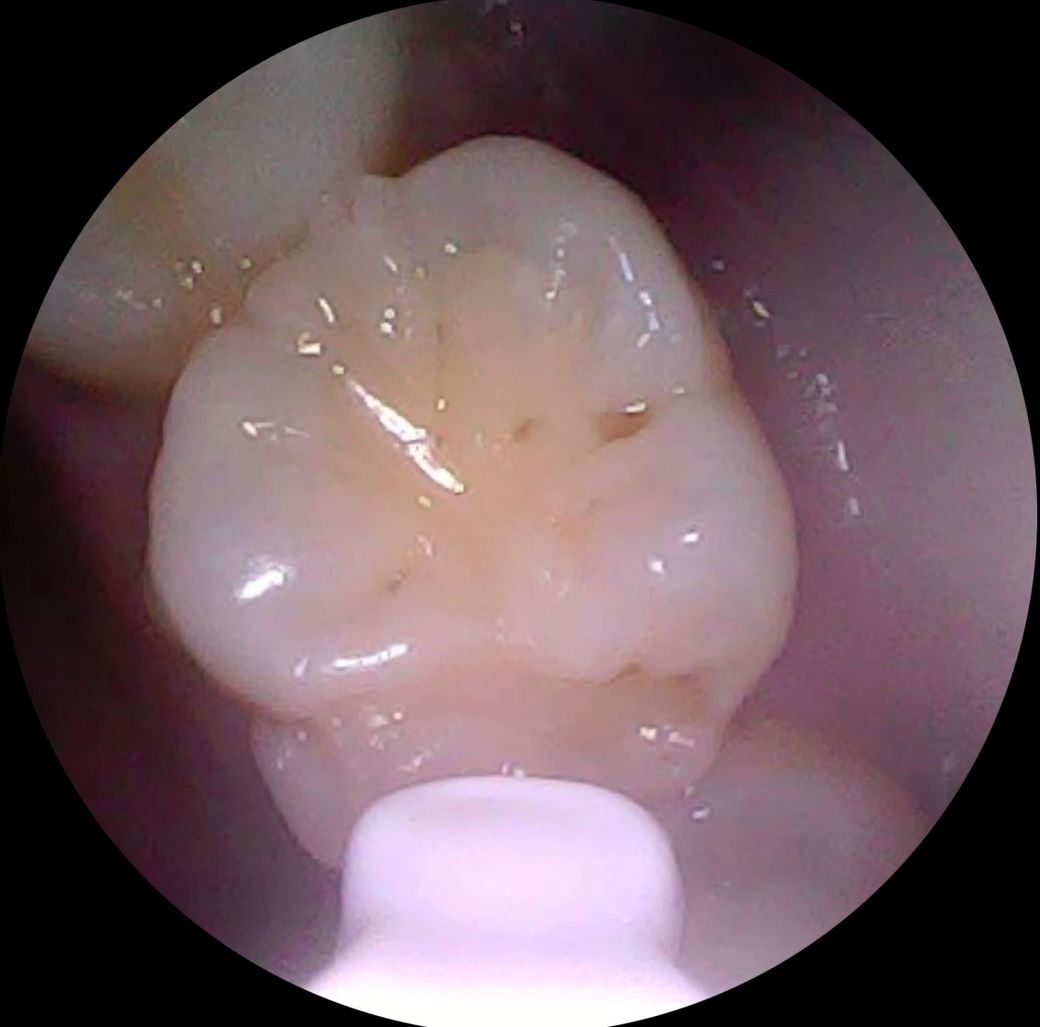

• 4번 째 사진

5번째는 치료해야할 것 같습니다

엑스레이를 찍어봐야 정확히 알겟지만,첫번째 치아는 충치가 상당히 진행된거 같고 나머지 치아의 충치는 간단한 충치 같습니다.